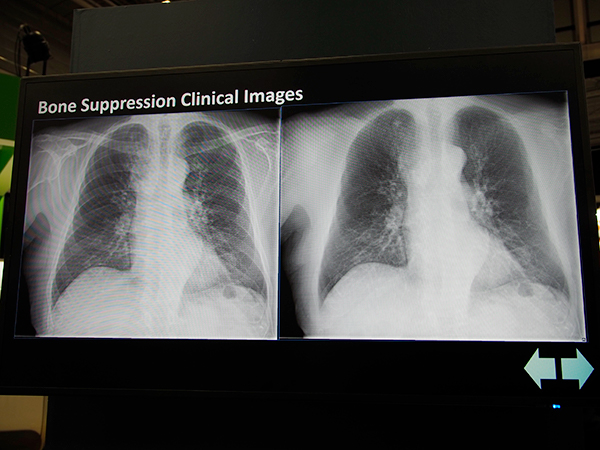

一般X線撮影装置「DigitalDiagnost C90」は,X線管にライブカメラを搭載し,撮影視野をライブ映像で確認することができる。これにより,適切な照射視野設定による被ばく低減や,確実な撮影による再撮影の抑制に貢献する。また,画像転送時に胸部の骨除去処理を自動で行う“Bone Suppression”も搭載可能となっている。

自動で胸部の骨除去処理を行う“Bone Suppression”